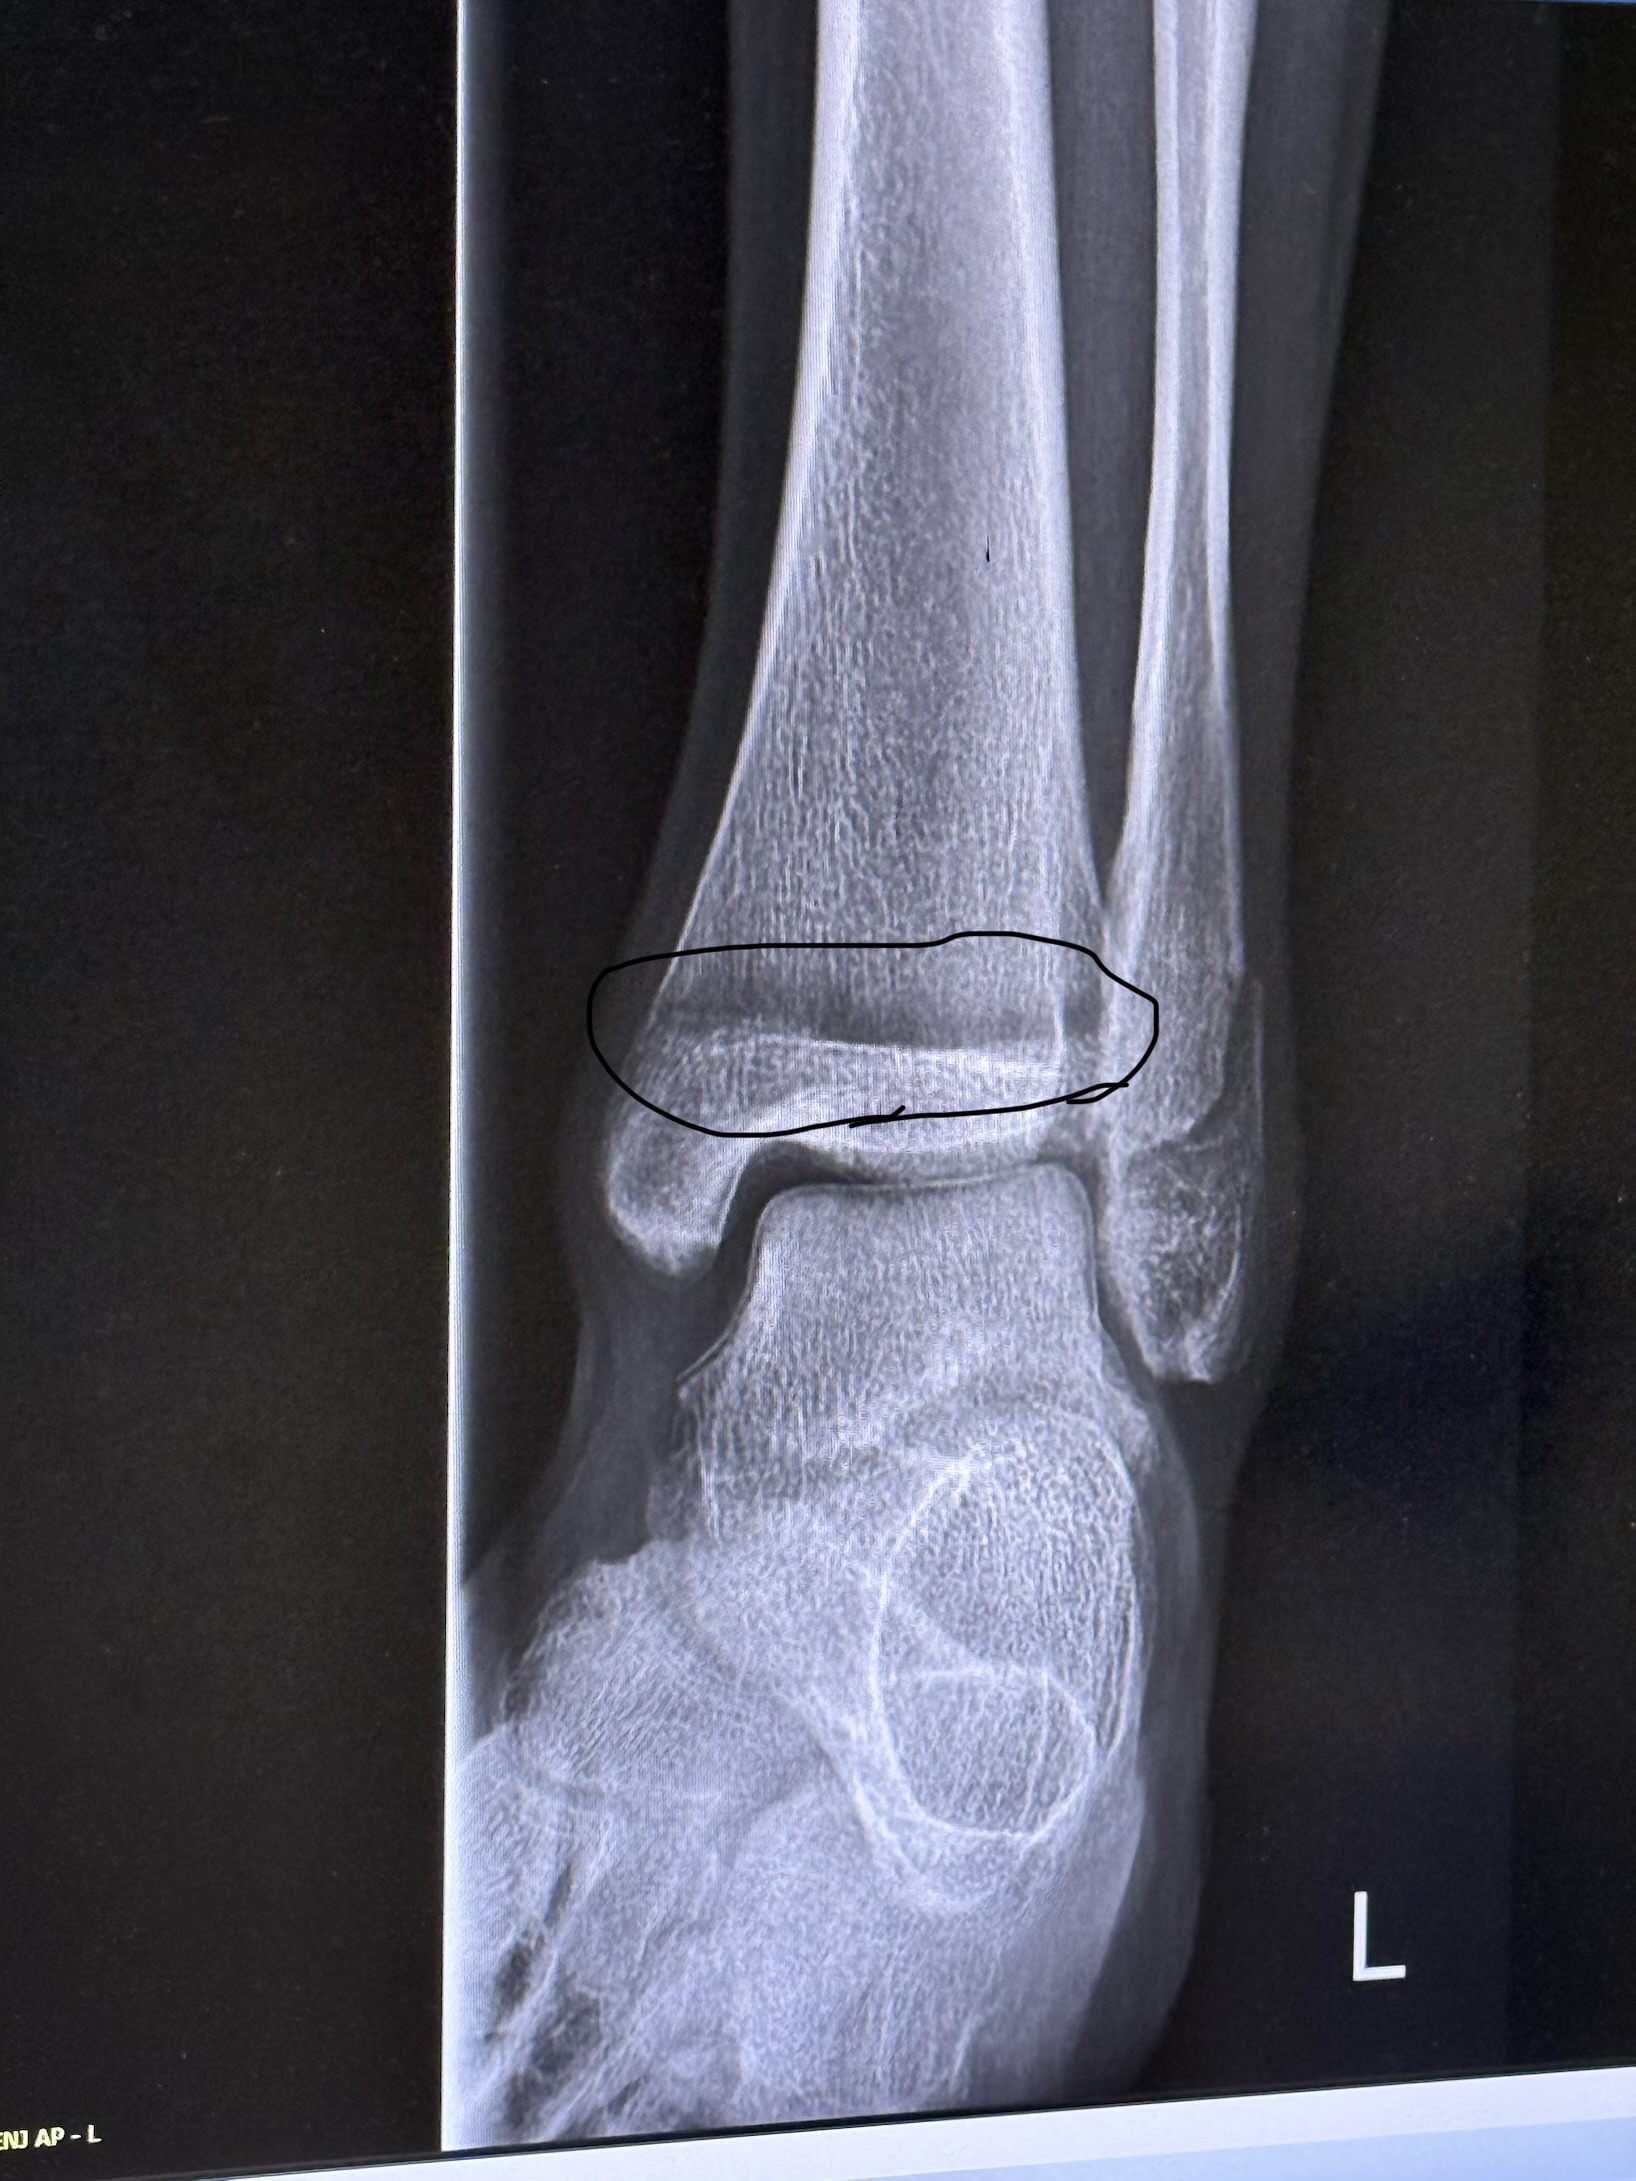

Are my growth plates still open ignore that circle

I dont know if you broke it on purposeto get the x ray but no its not closed and why would it be at 15

I am not an expert but they are close to closing I thinkIs my growth plate open?